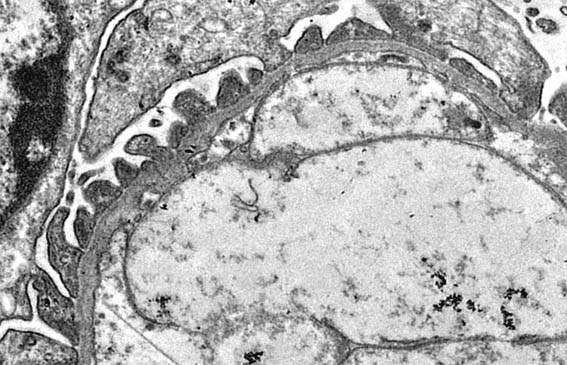

Figure 8. EM, original magnification X6,000; measured thickness of the GBM: between 180 and 220 nm.